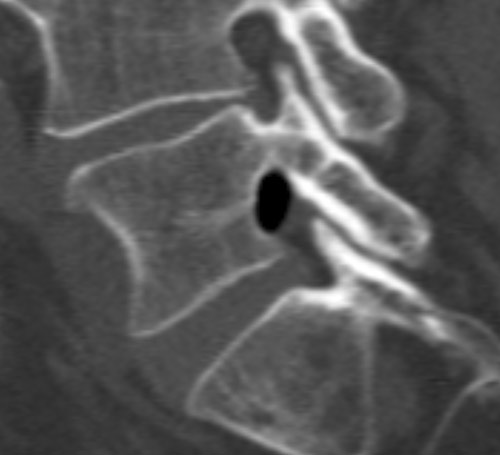

A man in his 60s was admitted to hospital with a two-day history of left-sided ischialgia and paresis development in L5 nerve innervated muscle. MRI showed a formation in the left lateral recess at L4/L5 level with dorsal dislocation of the left L5 nerve root. The formation had an unusually low MR signal giving rise to suspected calcification or the presence of air. A supplementary CT scan showed a well-defined collection of air in the same area (see images).

Clinical deterioration led to surgical exploration of the L5 root. Ventrally to the L5 root an amount of air was observable encapsulated in epidural soft tissue; an incision was made and the air released. Following this, the L5 root was softer to palpation and had free movement. The patient experienced considerable improvement postoperatively.

In our patient, there was only low grade disc herniation without rupture in the anulus fibrosus and slight facet joint arthrosis at the levels concerned. The air may represent gas formation from a sequestrum from an earlier prolapse, alternatively a gas-containing pseudocyst associated with the vacuum phenomenon in adjacent intervertebral disc spaces. It is difficult on this basis to explain the acute onset case history, but incision and release of the air build-up in the patient was nevertheless therapeutic.